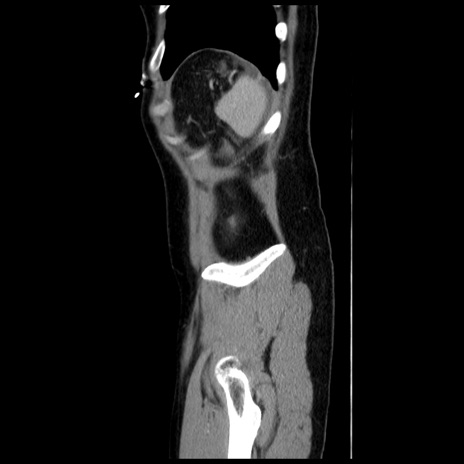

横断像

冠状断像

【症例】 50歳代女性

【主訴】 腹痛

【現病歴】前日生レバーを食べた。今朝に排便あり。 昼前に突然発症の腹痛を生じ、当院救急外来を受診した。

【既往歴】 子宮筋腫にてで子宮全摘後

【身体所見】 意識清明、腹部:平坦、軟、下腹部やや左を中心に圧痛・反跳痛あり、筋性防御あり

【データ】WBC 7800、CRP 0.07